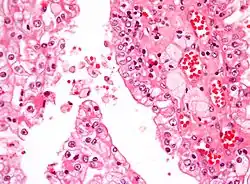

| Micrograph showing the most common type of kidney cancer (clear cell renal cell carcinoma). H&E stain. | |

The most common type of kidney malignancy is renal cell carcinoma,[35] which is thought to originate from cells in the proximal convoluted tubule of the nephron.[15][36] Another type of kidney cancer although less common, is transitional cell cancer (TCC) or urothelial carcinoma of the renal pelvis.[37] The renal pelvis is the part of the kidney that collects urine and drains it into a tube called the ureter.[37] The cells that line the renal pelvis are called transitional cells, and are also sometimes called urothelial cells. The transitional/urothelial cells in the renal pelvis are the same type of cells that line the ureter and bladder. For this reason TCC of the renal pelvis is distinct from RCC and is thought to behave more like bladder cancer.[37] Other rare types of kidney cancers that can arise from the urothelial cells of the renal pelvis are squamous cell carcinoma and adenocarcinoma.[15]

Renal cell carcinoma has been further divided into sub-types based on histological features and genetic abnormalities. The 2004 WHO Classification of the Renal Tumors of the Adults describes these categories:[41]

- Clear cell RCC